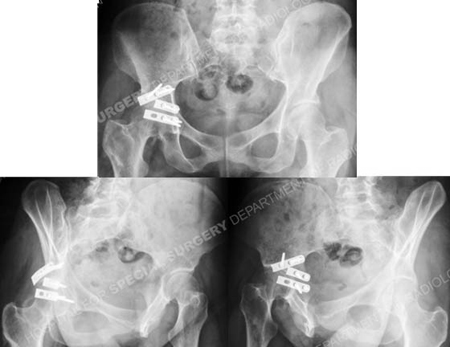

Anteroposterior and Judet radiographic views (Obturator Oblique and Iliac Oblique views)

at 5 months illustrating a healed Posterior Wall acetabular fracture.